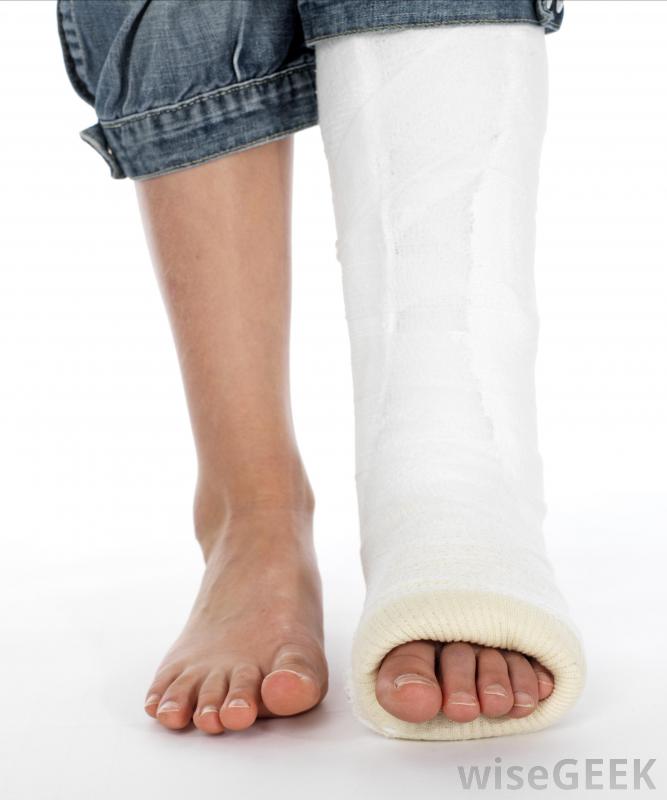

如何治療撕脫性骨折可能取決于幾個因素,其中包括骨折患者的年齡和損傷的嚴重程度。在許多情況下,撕脫性骨折可能不需要太多的治療,除了醫生的診斷和規定的休息時間外。當骨折代表更嚴重的損傷時,可以采用更廣泛的方法來治療撕脫骨折。石膏通常用于治療撕脫性骨折。當試圖評估如何治療撕脫性骨折時,它有助于了解這種類型的損傷是什么。在這種形式的損傷中,韌帶或肌腱通常是在劇烈的運動中,如投擲或跳躍時,從骨頭上拉出來。當這種情況發生時,韌帶或肌腱,因為它附著在骨頭上,所以可以帶走一塊骨頭如果沒有X光片,不可能知道與撕脫骨折相關的骨骼損傷程度。這種損傷聽起來非常嚴重,但在許多情況下,治療撕脫性骨折的黃金標準是讓人們休息,根據需要使用糖霜來消腫,可能還需要開一些消炎藥來幫助減輕炎癥。休息時間可以持續兩到六周,這取決于損傷的嚴重程度。通常情況下,這足以讓骨骼重新附著并愈合一些醫生計劃在一個設定的時間點進行后續的x光檢查,以確保再次附著成功。對撕脫性骨折進行冰敷可能有助于減輕腫脹雖然上述治療撕脫性骨折的方法在很多情況下都可以使用,但有時需要更大的干預來處理這種損傷。有時當肌腱或韌帶拉傷時,在這個過程中,它會受到嚴重的損傷。這種損傷將使骨骼無法正常地縫合在一起,并可能影響骨折部位的功能。在這種情況下,可能需要手術修復韌帶或肌腱損傷另一個值得關注的問題是當兒童發生撕脫性骨折時。孩子們通常會沿著骨生長板發展這些骨折。當這些骨折影響到生長板時,人們真的擔心骨骼不能正常地結合在一起,這可能會在生長過程中導致畸形。醫生可能會治療撕脫傷在生長板上發生的骨折通過手術來確保愈合是完全促進的,受傷區域不會影響將來的生長。應該注意的是,人們不建議在家里治療任何形式的骨折撕脫骨折可能看起來更為良性,至少在某些時候,如果沒有x光和醫生檢查,不可能知道骨或組織損傷的程度所有懷疑自己骨折的人都應該去看醫生以獲得診斷和正確的治療建議。在某些情況下,有必要進行手術來修復撕脫性骨折過程中受損的肌腱或韌帶。